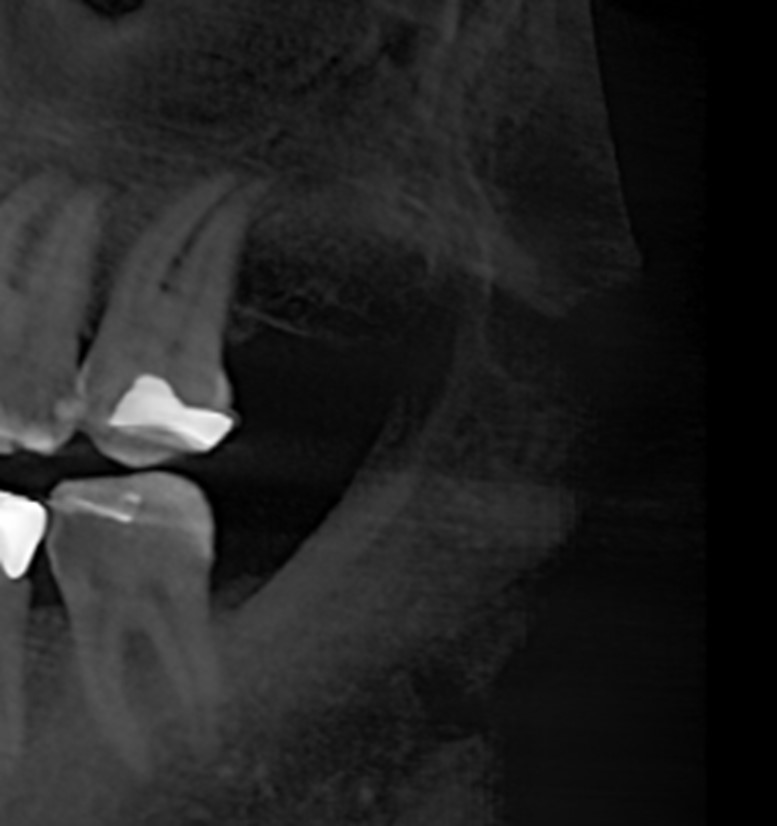

Diagnosis often involves advanced imaging techniques like cone beam computed tomography (CBCT), enabling precise identification and assessment of these cavitations. Early detection and appropriate treatment are crucial for preventing further complications and restoring dental health.

Treatment with Cone Beam Tomography

Our clinic offers advanced solutions utilizing Cone Beam tomography technology, the most widely used in the United States. This approach allows us to detect many dental conditions, including cavitations, with precision and efficiency.

Through a thorough examination and the use of Cone Beam tomography, we accurately identify areas affected by dental cavitations.